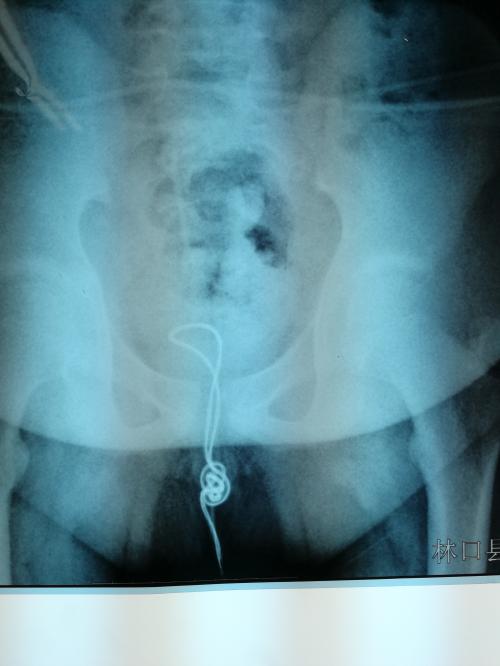

次日一早,小明的父母带他来到哈市儿童医院,拍片结果显示,一根10厘米左右的线盘在膀胱内,已经有了炎症,最可怕的是线在膀胱内已经打结,一旦将线强行拉出就会损伤尿道壁造成二次伤害。医生将尿道切开2厘米的小口,将异物取出,手术非常顺利。